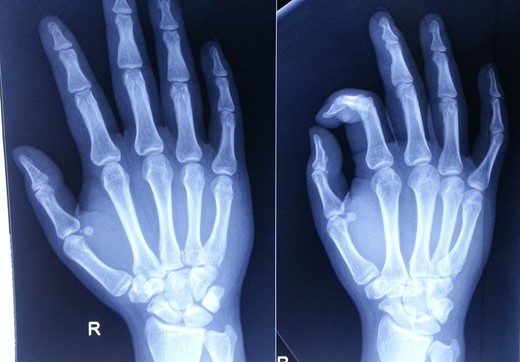

A 28-year-old gentleman presented to us with complaints of pain and swelling of the right hand for 2 hr. He sustained an injury to his hand when his motorbike skid and he landed on the ulnar aspect of his hand and little finger. On examination, there was swelling, tenderness and deformity on the ulnar aspect of his hand. There was restriction of movement of the fifth finger. His wrist movements were normal, and there were no open wounds in hand. Radiological evaluation revealed dorsal dislocation of fifth CMC joint and volar dislocation of distal MCP joint (Fig. 1). Based on clinico-radiological examination, diagnosis of close, fifth floating finger was made. Closed reduction of the dislocations was done under sedation in emergency room, and wrist splint supporting the head of MCs was applied. Immediate post-reduction stability of the joints was assessed and the joints were found to be stable. Post-reduction radiographs (antero-posterior and oblique views) confirmed the reduction of both CMC and MCP joints (Fig. 2). The splint was removed after 3 weeks, and finger and wrist range of motion (ROM) exercises were started. At 6 months follow-up, his finger and wrist ROM were full. Grip strength was comparable on both sides and his movements were pain free (Fig. 3). No abnormalities were detected on the radiographs at 6 months follow-up (Fig. 4).